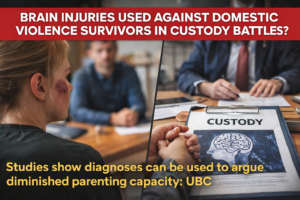

UBC researchers receive $3.4M to address brain injuries in survivors of intimate partner violence

UBC

,

June 2024